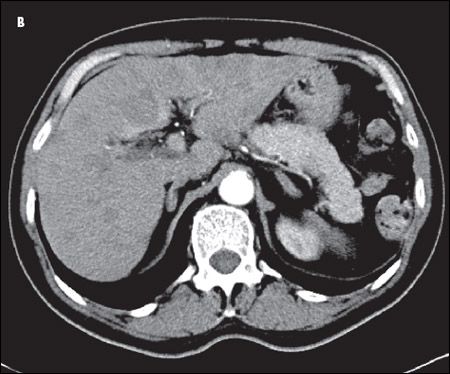

A CT scan of the chest showed an amorphous soft tissue mass that encased and constricted the right main pulmonary artery and the right main stem bronchus (A). Extensive round masses were visible in the liver; the largest mass was in the right medial hepatic lobe and measured 2.7 × 2.4 cm (B).

SCLC typically presents as a large central mass (as in this patient) with mediastinal adenopathy. SCLC can infiltrate the submucosa, causing either intrinsic or extrinsic compression of the bronchi. SCLC has a propensity for spreading to the liver, brain, bone, and bone marrow. The neutropenia and thrombocytopenia seen in this man can be explained by the infiltration of his bone marrow by the SCLC. In a series of 129 patients with SCLC, 30% had bone marrow involvement. However, in only 2.3% was the bone marrow the only site of metastatic disease.7 Other presenting symptoms include cough, dyspnea, hemoptysis, chest pain, postobstructive pneumonia, and the paraneoplastic syndromes mentioned above.